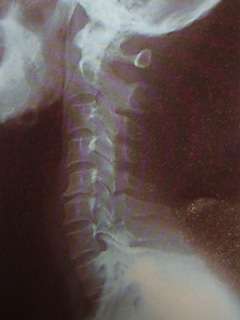

ストレートネック

最近、まきのブログで病弱なように書かれてますが、病気じゃなくって肩こりから来る頭痛にまいってます。 今日は、子供の用事があって丁度仕事を休む予定の日で、午前中時間があったので病院に行ってみました。 通常、首の骨がS字で頭… 続きを読む ストレートネック